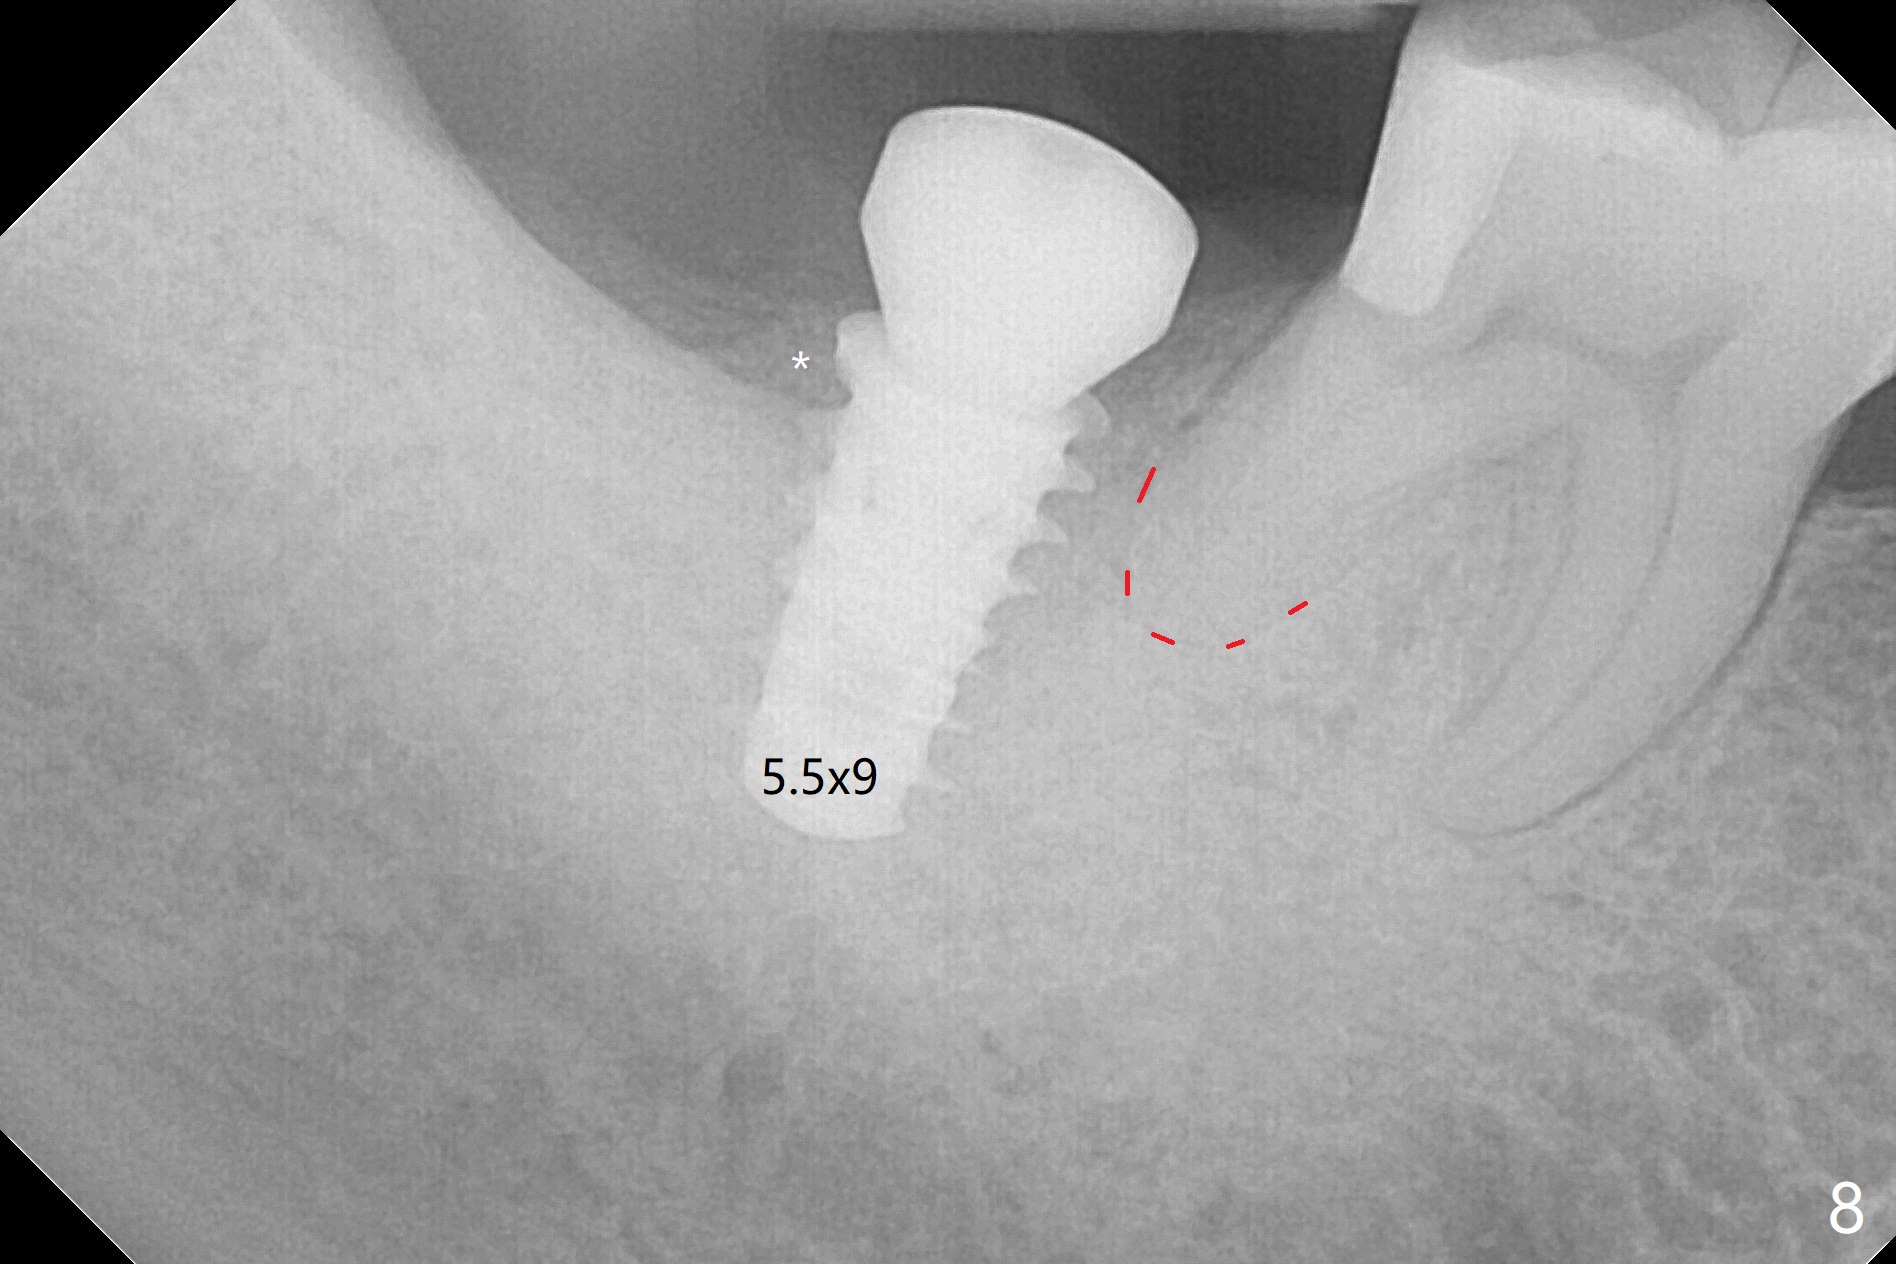

The socket shrinks with buccal plate reduction 3 months post socket preservation (Fig.5), as compared to 10 days postop (Fig.4). To restore the socket as much as possible, Magic Split is used (flapless), followed by Magic Expanders 3-3.8 mm for 11 mm (gingival level) and a 4x11mm dummy implant (Fig.6). The osteotomy is moved distal by using Lindamann bur; following 3.8 mm Magic Drill, a 4.5x11 mm dummy implant (Fig.7). Finally a definitive 5.5x9 mm implant is placed with <45 Ncm; a 6x2 mm healing abutment is placed to close the access (Fig.8). Autogenous bone harvested from the Magic Drill returns to the osteotomy mainly buccal prior to implant placement (Fig.8 *). The patient reports no discomfort immediately postop, thanks to the flapless technique. The patient has had postop pain; 11 days postop, the abutment and implant are found to be loose. After re-tightening by hand, the complex is seated deeper and more stable (Fig.9 arrow).